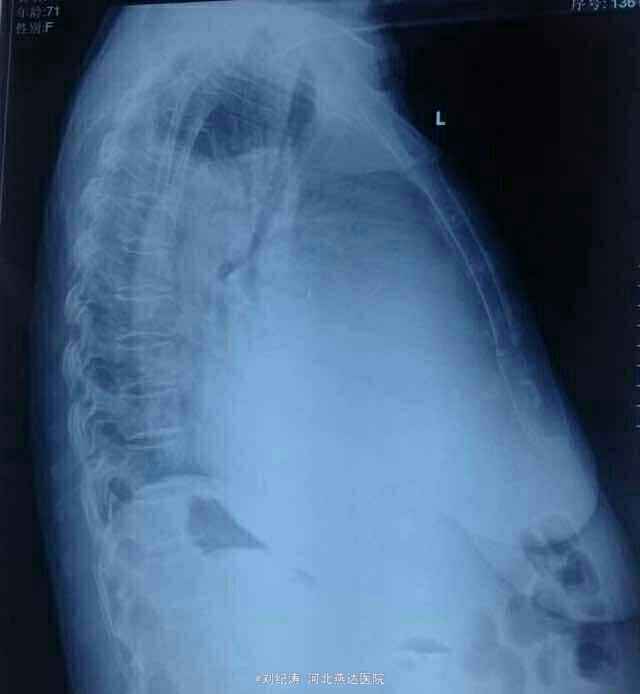

查体:心率78次/分,血压104/72mmHg,端坐体位,双侧胸廓对称,右肺语颤增强,右肺呼吸音弱,左肺呼吸音正常,心律齐,腹部膨隆,腹水征阳性,移动性浊音阳性,双下肢轻度凹陷性水肿。 辅助检查: 胸片:1、右侧胸腔积液,2、左心室增大(有心衰影像表现)。心脏彩超:EF21%,全心扩大,二尖瓣关闭不全,三尖瓣关闭不全(中度)并肺动脉高压,心功能减低。 腹部彩超:肝脾双肾未见明显异常,胰腺显示不清,腹腔积液(深约11cm)。 妇科彩超:未见明显异常。 肿瘤标志物:CA199:91.58U/ml,CA125:>400U/ml. 胸腹水脱落细胞学检查未见癌细胞。

拟诊:1、扩张性心肌病 二、三尖瓣关闭不全 慢性心功能衰竭 2、右侧胸腔积液 3、腹腔积液(肿瘤不除外) 治疗:入院后完善检查,考虑心源性所致,给予胸腹腔穿刺置管流胸腹水(交叉放水),强心利尿、抗炎、扩管、纠正心衰及对症治疗一周,腹水明显减少,胸水未见明显减少,此时肿瘤标志物回示:CA125、CA199升高,遂行妇科彩超排除妇科肿瘤,结果未见异常,欲行CT进一步检查,患者家属未接受;继续引流胸水及对症治疗3天,患者腹胀、气喘症状明显好转,胸腔积液较前减少,欲行胸部CT进一步检查,患者未接受,切见症状好转,要求出院,反复劝说无效后予以出院。出院继续口服强心利尿药物。

随访:患者20天后门诊复查彩超:右侧胸腔积液深约5cm,腹腔少量积液;患者无胸闷、气喘、腹胀不适。 讨论:在诊断方面,首要考虑心源性,其次是肿瘤性,肿瘤标致物不是特异指标,CA125增高可见于卵巢癌,浆膜腔恶性积液,淋巴瘤,盆腔炎症,CA199升高有胰腺癌,胰腺炎,其他消化道肿瘤等。肿标的持续升高对诊断肿瘤意义更大。 肺癌继发恶性腹水的临床上真心罕见,反倒是消化道、卵巢恶性肿瘤继发恶性胸水的多见。 左心衰或者全心衰竭可以仅仅出现单侧胸腔积液,并且可以是大量的,甚至是血性的,此外心衰引起的胸腔积液有个特点,就是如果是单侧,右侧多见,如果是双侧的话,右侧积液量多于左侧,关于这个特点,文献里有报道,大家可以查一下,解释的原因较多。而这个患者的胸腔积液就在右侧,在排除右侧有肺炎,肿瘤等可引起胸腔积液的其他疾病后,首先就要考虑心衰所致,患者胸片心影明显增大,最重要的是心脏彩超汇报全心扩大,射血分数21%,扩张性心肌病等,因此诊断心力衰竭应该没有问题!心力衰竭,特别是全心衰竭引起胸腹腔积液是可以的。对于心衰引起的这么大的胸腔积液,有时候易被误诊误诊,患者胸腔积液消失慢,如果是心衰所致,那么真正的治疗方法就应该是强心利尿扩血管等,并且用量用药方面有时候要个体话,否则胸腔积液即使抽了还会长,因为本质原因心衰没有得到纠正。 对于该患者胸腹水病因:心源性?肿瘤性?或者其他?您有什么看法?